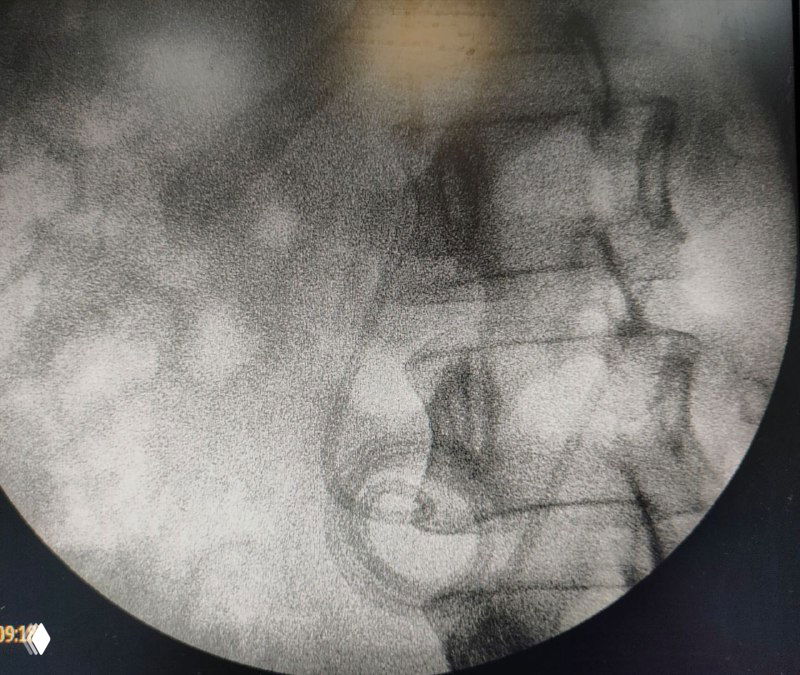

Установка игл Джамшиди перед вертебропластикой

Фото установки игл Джамшиди в тело позвонка перед пункционной вертебропластикой: проколы кожи, рентген‑контроль и последующее введение костного цемента.